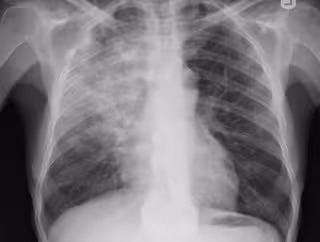

Neumonía, pulmonía, radiografía pulmones

FLICKR/YALE ROSEN

La neumonía es una infección pulmonar especialmente frecuente en ancianos, niños, personas inmunodeprimidas y pacientes con patologías crónicas como: enfermedad pulmonar obstructiva crónica (EPOC), cardiopatía crónica, insuficiencia renal, cáncer, cirrosis hepática y diabetes. En cualquiera de estos casos, la neumonía se origina por una reacción inflamatoria de los alveolos pulmonares, causada a su vez por agentes infecciosos como virus, hongos o bacterias.